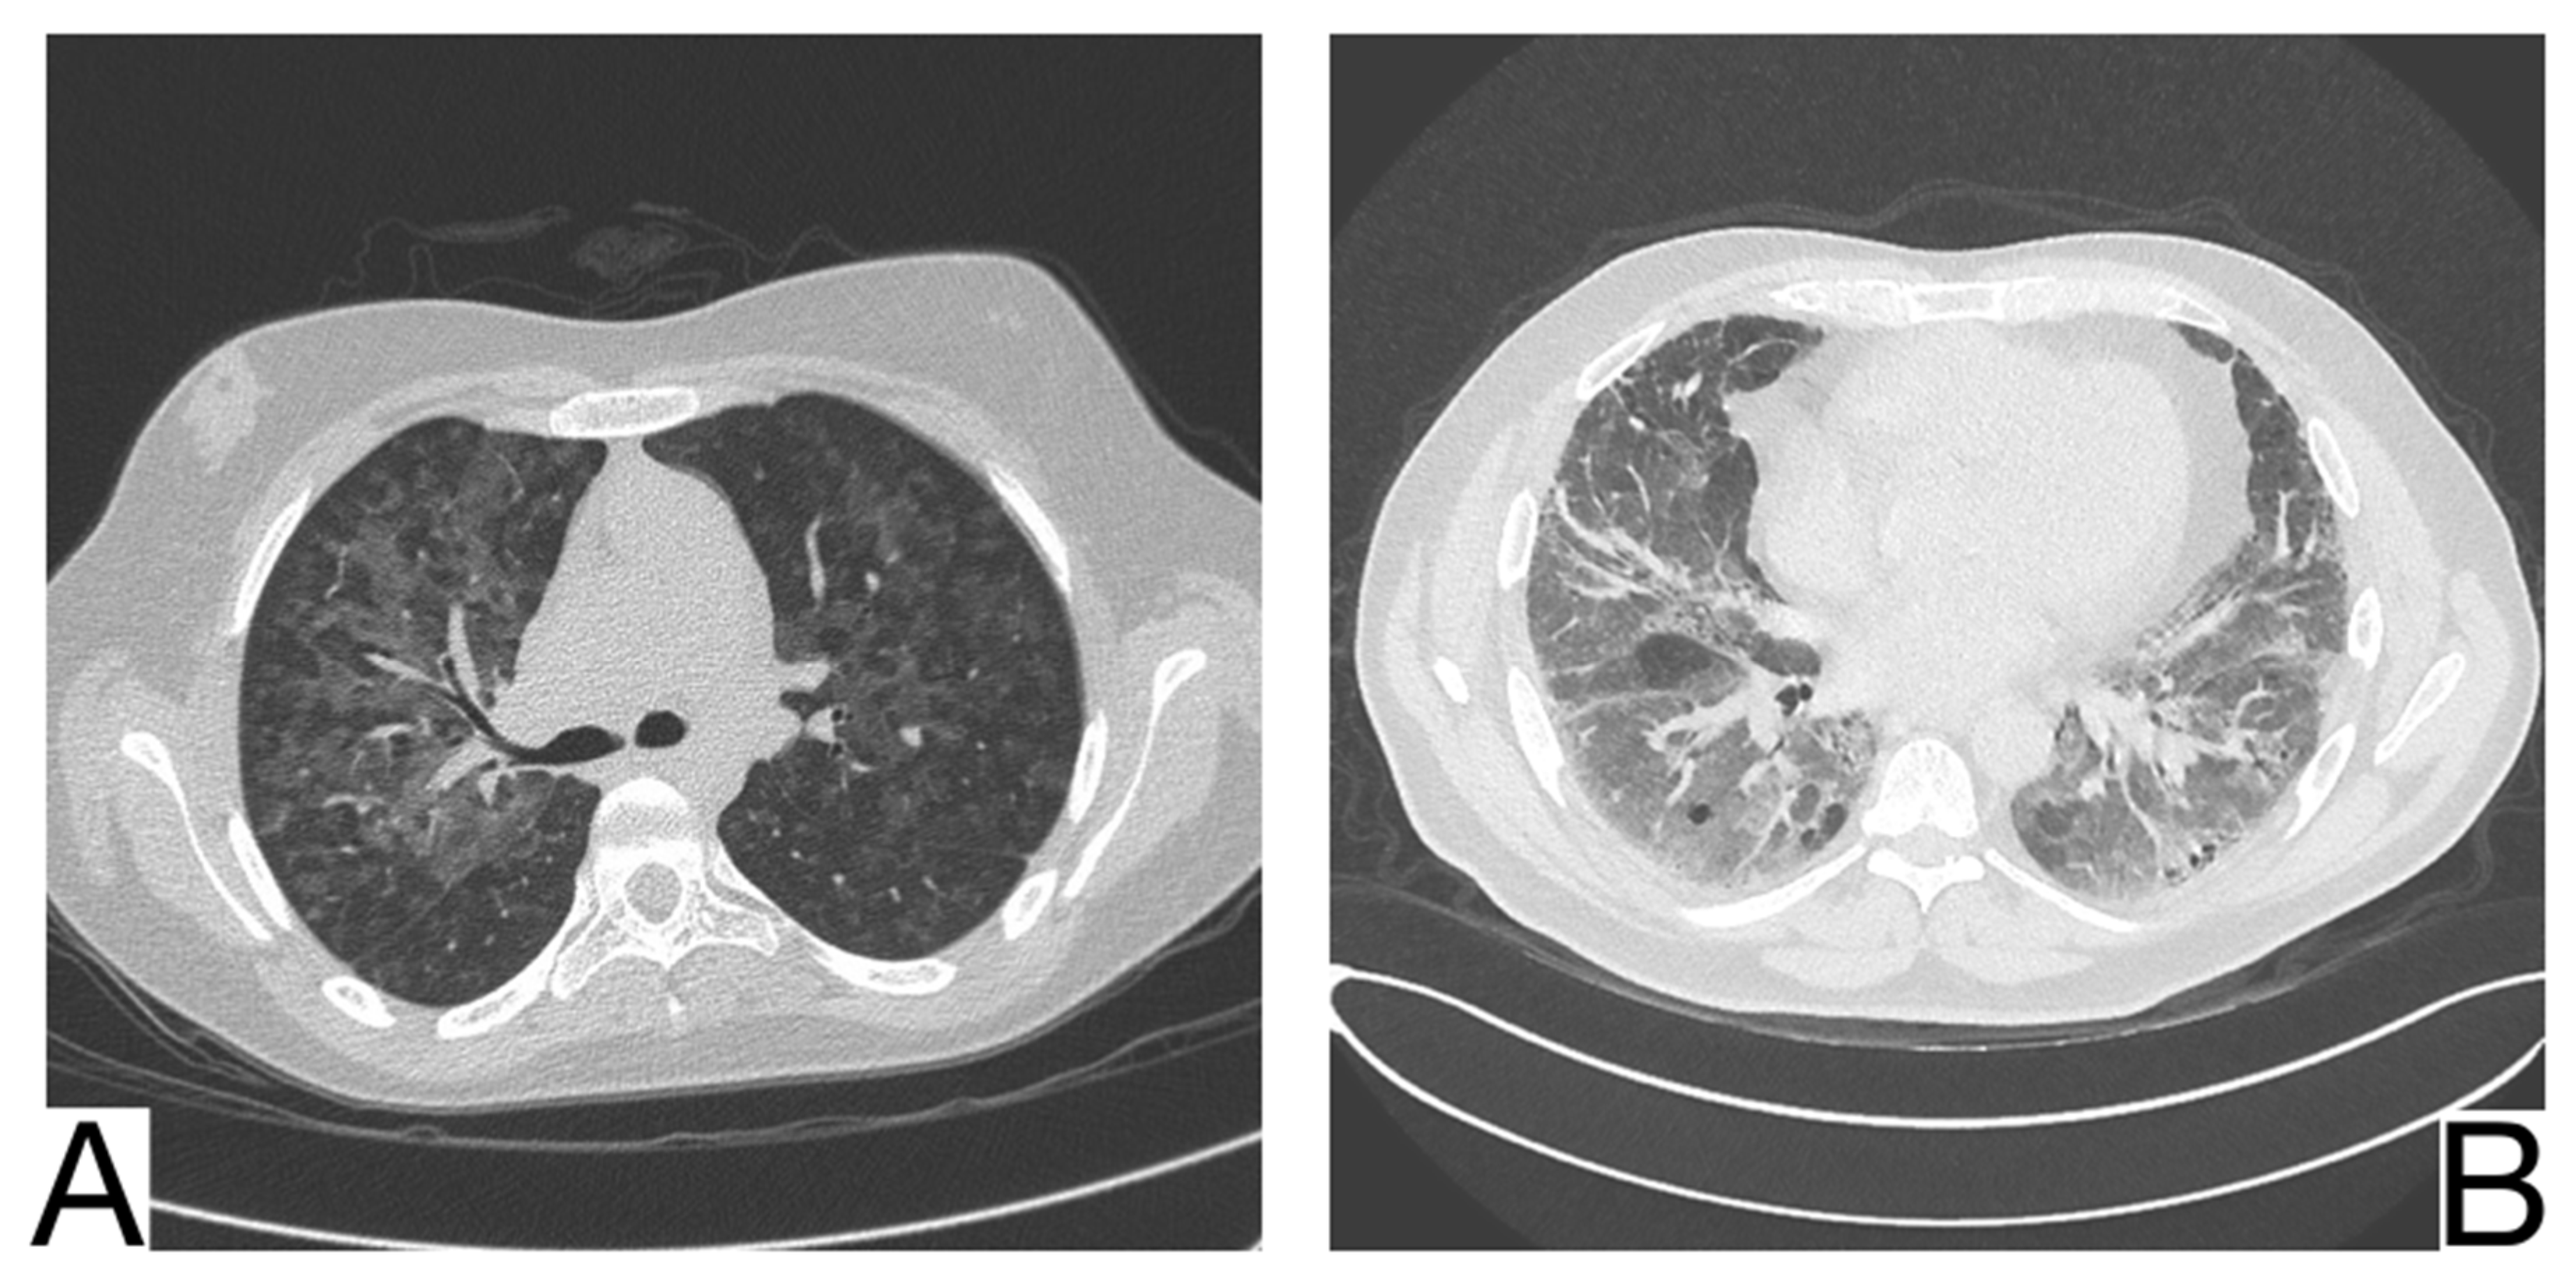

COVID-19 Pneumonia

10.2. Viral Pneumonia